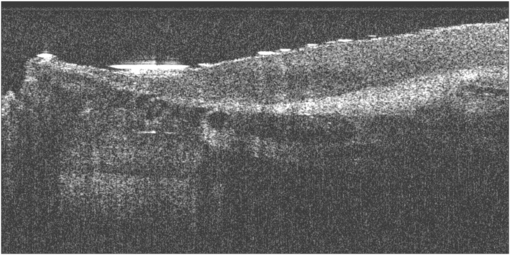

OCT is based on interferometry i.e. the interference between reflected light and a reference beam, which is used as a coherence gate to isolate light from specific depths. A Michelson interferometer is often used to perform the low-coherence interferometry for OCT (Fujimoto et al 2000). The frame rate for early OCT systems was typically 4 to 8 fps but faster modern systems are available at beyond video frame rate (depending on imaging parameters). A schematic representation of an OCT system is shown in figure 19 and example OCT B-mode image in figure 20.

Standard image High-resolution imageFigure 20. Example OCT B-mode scan of tissue formed from a sequence of axial line (A-) scans. Cross-sectional images are constructed by performing measurements of the echo time delay of light at different transverse positions. The result is a two-dimensional data set which represents the backscattering in a cross-sectional plane of the tissue. This data can be displayed as a grayscale or false colour image (permission granted to re-use from Fujimoto et al 2000 Neoplasia 2 9–25, copyright Elsevier). A sequential series of these B-mode images across the tissue can be combined to form a 3D image.

An example OCT image of the nailfold skin in a patient with SSc is shown in figure 22. The cross-sectional view indicates the region of dilated blood vessels. This imaging shows the fine static detail of the tissues and a further advancement of the technique would be to superimpose Doppler OCT blood flow information onto the image (Mason et al 2004).

Figure 22. Example OCT B-mode scan giving a cross-section of the finger nailfold region in a patient with systemic sclerosis (SSc). The nailfold region is to the upper left hand part of the image, with the darkest circular regions indicate the dilated capillary region. Skin thickness assessments have also been described in Abignano et al (2013).